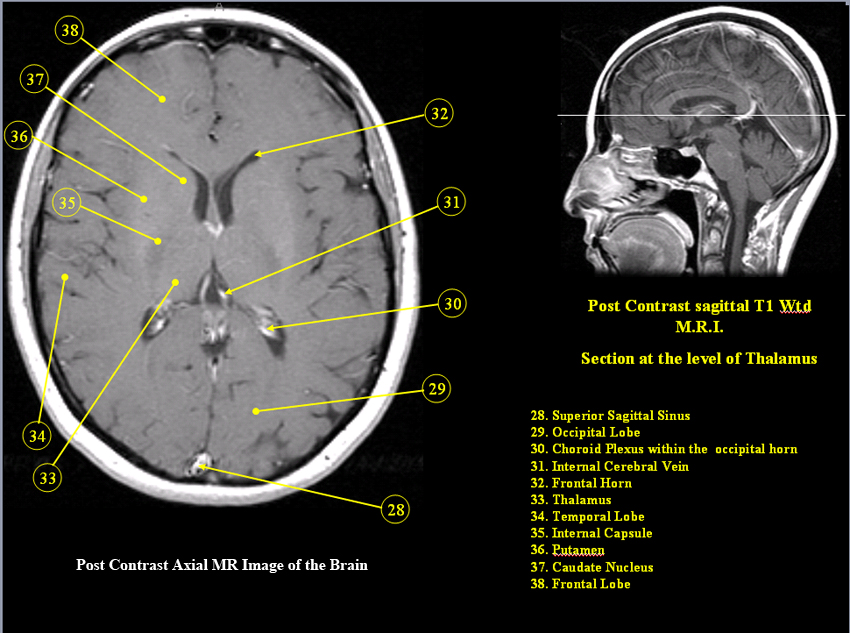

Approach To Mri Brain